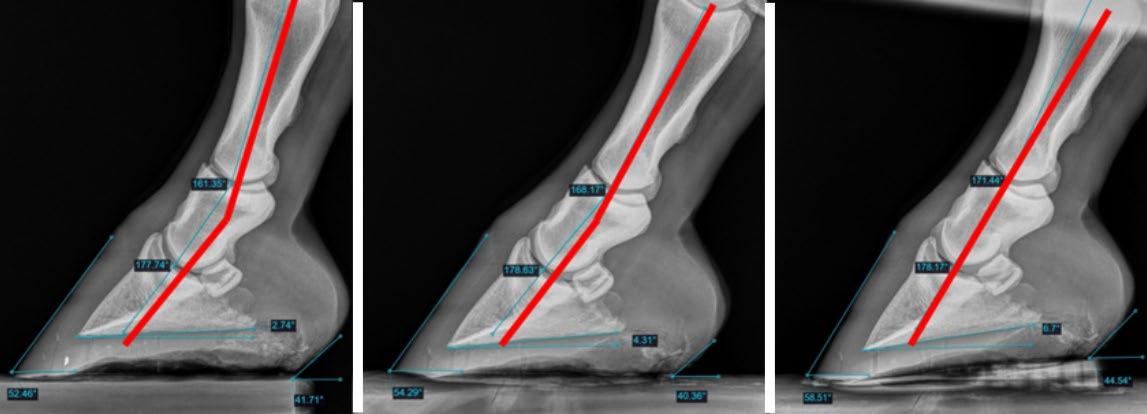

Radiographic examination revealed above average linear bony column alignment of the distal phalanges (P1, P2, P3) with a palmar angle of 3.7o on the left forelimb and 6.4o on the right forelimb. There were no significant mediolateral imbalances radiographically.

mimic barefoot biomechanics and remove heel restriction as much as possible using a “FlipFlop” pada and an aluminium breakover shoeb cut in half (Figure 3). The mare remained in the “Flip-Flops” for 3 months with no reported issues in lameness or performance observed during this time. Follow-up examination was performed prior to the 3rd set of shoes being placed. The mare’s heels had visibly lowered on both front feet, especially the lower left forelimb. Radiography showed that the mare was now at a zero-degree palmar angle on both front feet. However, physically, her limbs had relaxed and her

carpus was fully engaged. The owner, who was very diligent and observant, stated that there was only progress in her movement and demeanour and was pleased with the response, despite the obvious deterioration in palmar angle observed radiographically. There are many factors that may have been at play with this occurring: 1) the original farrier was injured during this time and an apprentice was shoeing the horse, 2) the shoeing changes occurred during a very wet winter which may have contributed to softening of the hoof capsule, 3) anecdotally, I have often observed sound, barefoot horses to have ground-level palmar angles but having wide heel bulbs and the appearance of a healthy frog and digital cushion, so more research into average palmar angles in shod versus unshod horses may be needed in the future to define what truly is “normal.” However, the vast amount of research showing a straight hoof-pastern axis and linear phalangeal alignment being the target biomechanical “ideal” has the most merit to maintaining soundness in performance horses and is still the goal for this horse.

Due to the deterioration in palmar angles, it was necessary to change the shoeing package to a 3-degree frog-support padc to support the heels and allow the palmar angle to return to normal. Photos of the mare were taken with the new shoeing package placed and the relaxation in the forelimbs is visible when compared with the mare’s original posture (Figure 5) even though the internal phalangeal alignment and palmar angle is radiographically similar.

and 5 shoeing cycles (Figure 6). The owner reported no issues with lameness and emphasized that the mare seemed to be improving month-on-month. A follow-up exam was performed at 6 months. There was improvement in palmar angles on both front feet, with the left forelimb at 2.7o and the right forelimb at 6o. The overall hoof quality had improved, with minimal evidence of horn tubule compression and abnormal growth rings. The right fore had made the most dramatic improvement and was moved to a flat frog-support pad at this stage. The left forelimb was trimmed to a 4-degree palmar angle but still required a degree pad (Figure 6) to restore phalangeal alignment based on this horse’s conformation.

Figure 6: Left image - alignment at shoe removal prior to trim. Middle image - alignment after trimming. Right image - alignment with 3-degree pad in place to demonstrate appropriate linearity. Figure 7: Comparison of Day 1 (left pair) through 9 months of hoof rehabilitation (right pair).

Figure 8: Upper 2 rows – LF, clinical and radiographs. Lower 2 rows – RF, clinical and radiographs. Left to right clinical and radiographic pairs of images - Day 1 before new shoes; 3 months with Flip-Flops; first caudal support package; after 6 months in caudal support. Notice the health and integrity of the hoof walls (column 4) relative to the original photos (column 1). 103293. https://doi.org/10.1016/j.jevs.2020.103293.